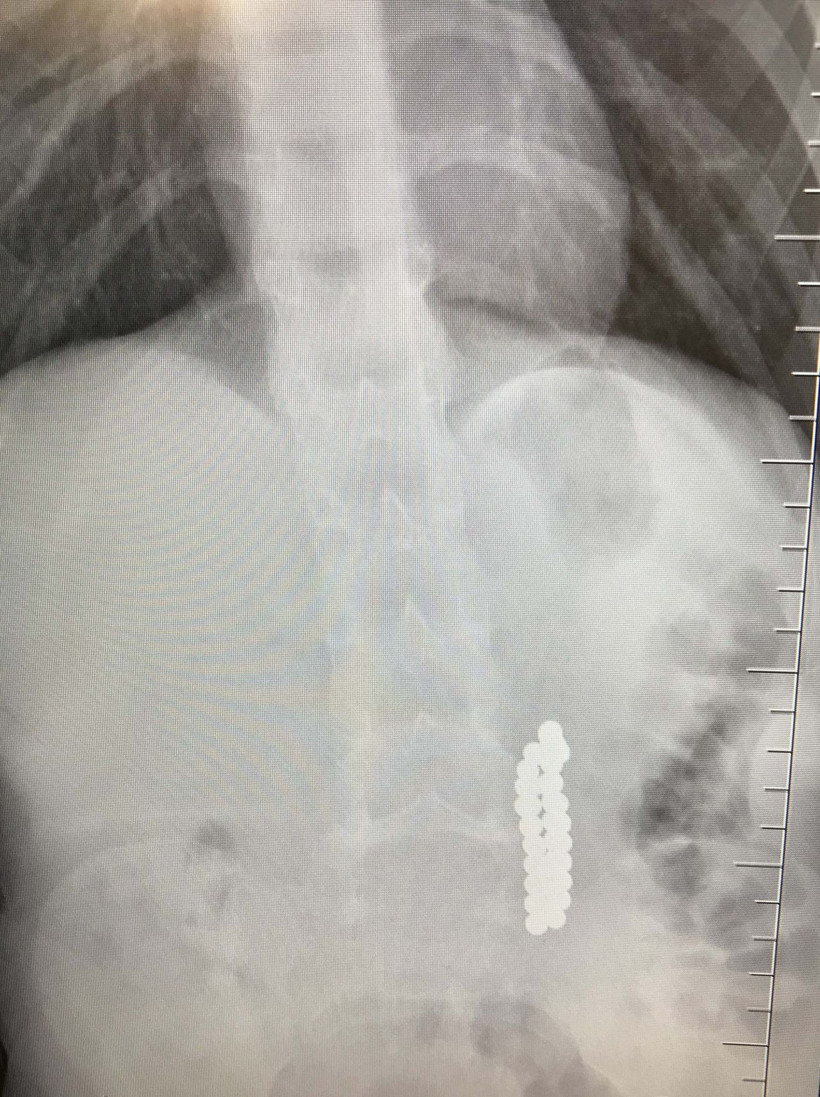

İstanbul Beylikdüzü’nde kusma karın ağrısı şikayetiyle hastaneye getirilen 9 yaşındaki çocuk çocuğun röntgen filmi çekilince gerçek ortaya çıktı. Oyuncak olarak satılan stres bilyeleri olarak da bilinen neodyum adlı güçlü mıknatıstan 42 adet bağırsağında tespit edildi. Ameliyata alınan çocuğun delinen bağırsağından mıknatıslar çıkarıldı.

Birkaç gün sonra şiddetli karın ağrısı ve kusma şikayeti ile hastaneye gelen çocuğun röntgeni çekildi.

Röntgen filminde çocuğun midesinde boncuklar halinde yabancı bir cisim tespit edildi.